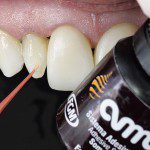

A figura 29 evidencia a aplicação do adesivo monocomponente (Ambar) sobre o esmalte e dentina com um Cavibrush. É importante salientar que o esmalte pode estar seco ou úmido, mas a área de dentina exposta, neste caso a cervical, deve ser previamente reidratada.

- Figura 29